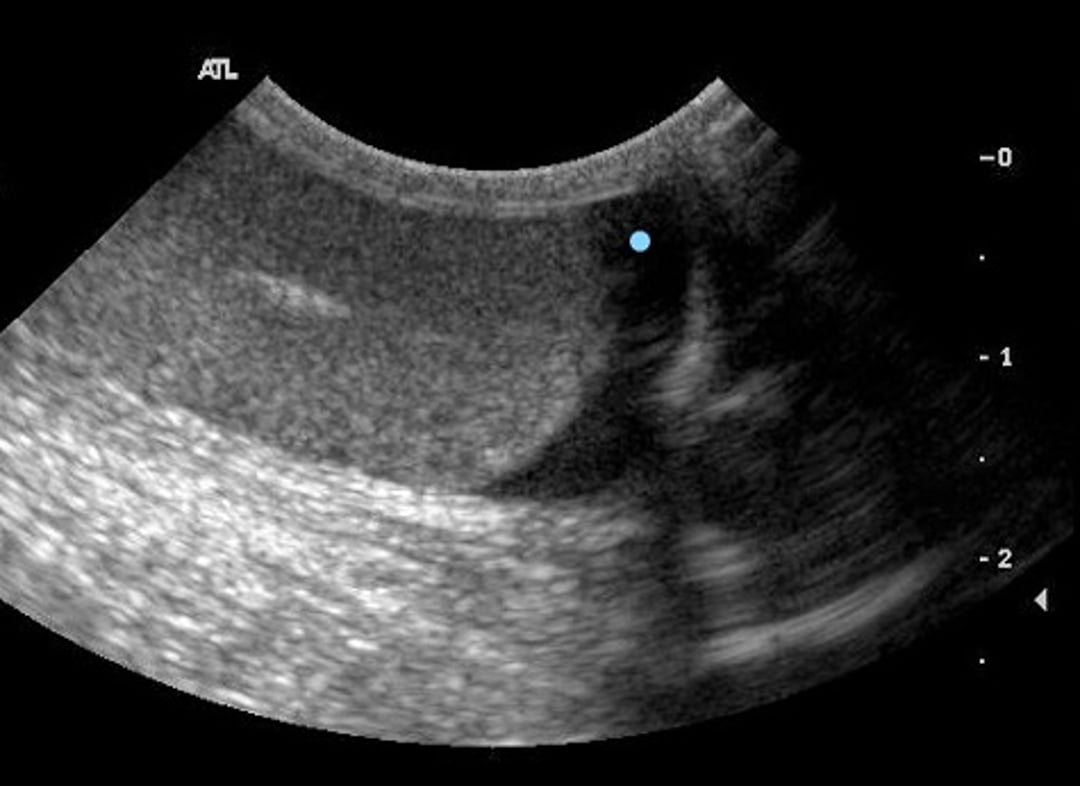

Ecografía sagital del escroto de un perro con orquiepididimitis. Observe la región anecoica mal definida (punto azul) indicativa de edema.

Cortesía de la Dra. Autumn Davidson.